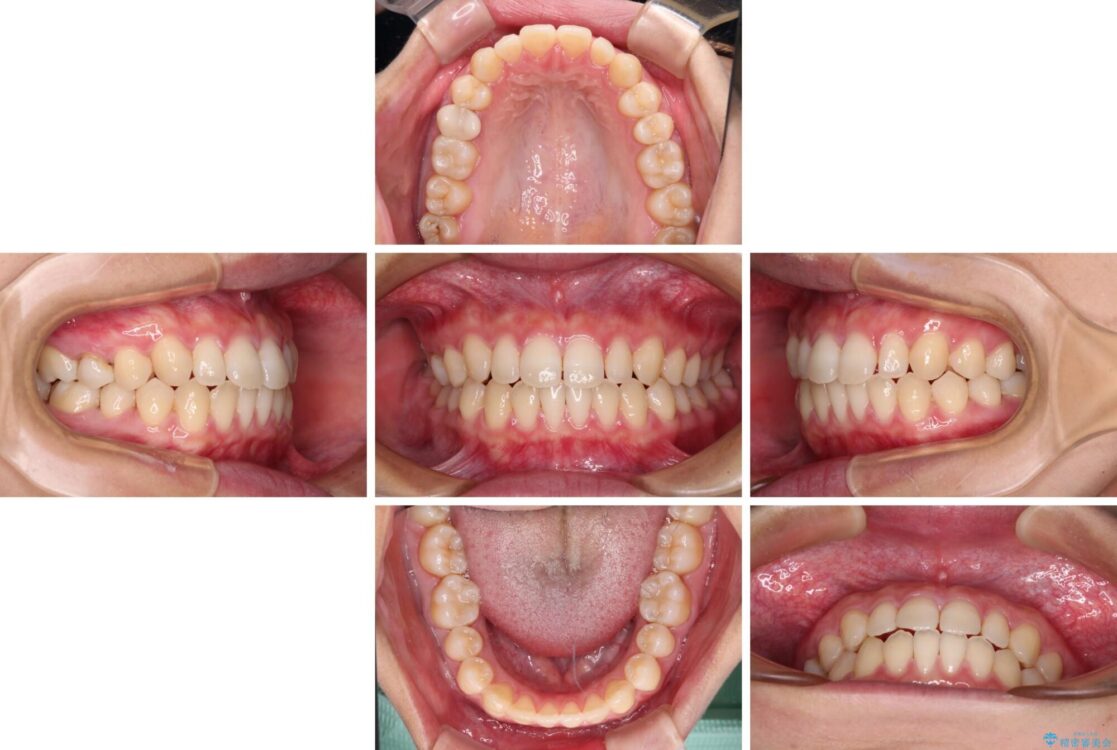

治療後

• 隙間だらけの歯列 インビザラインで改善 治療後画像